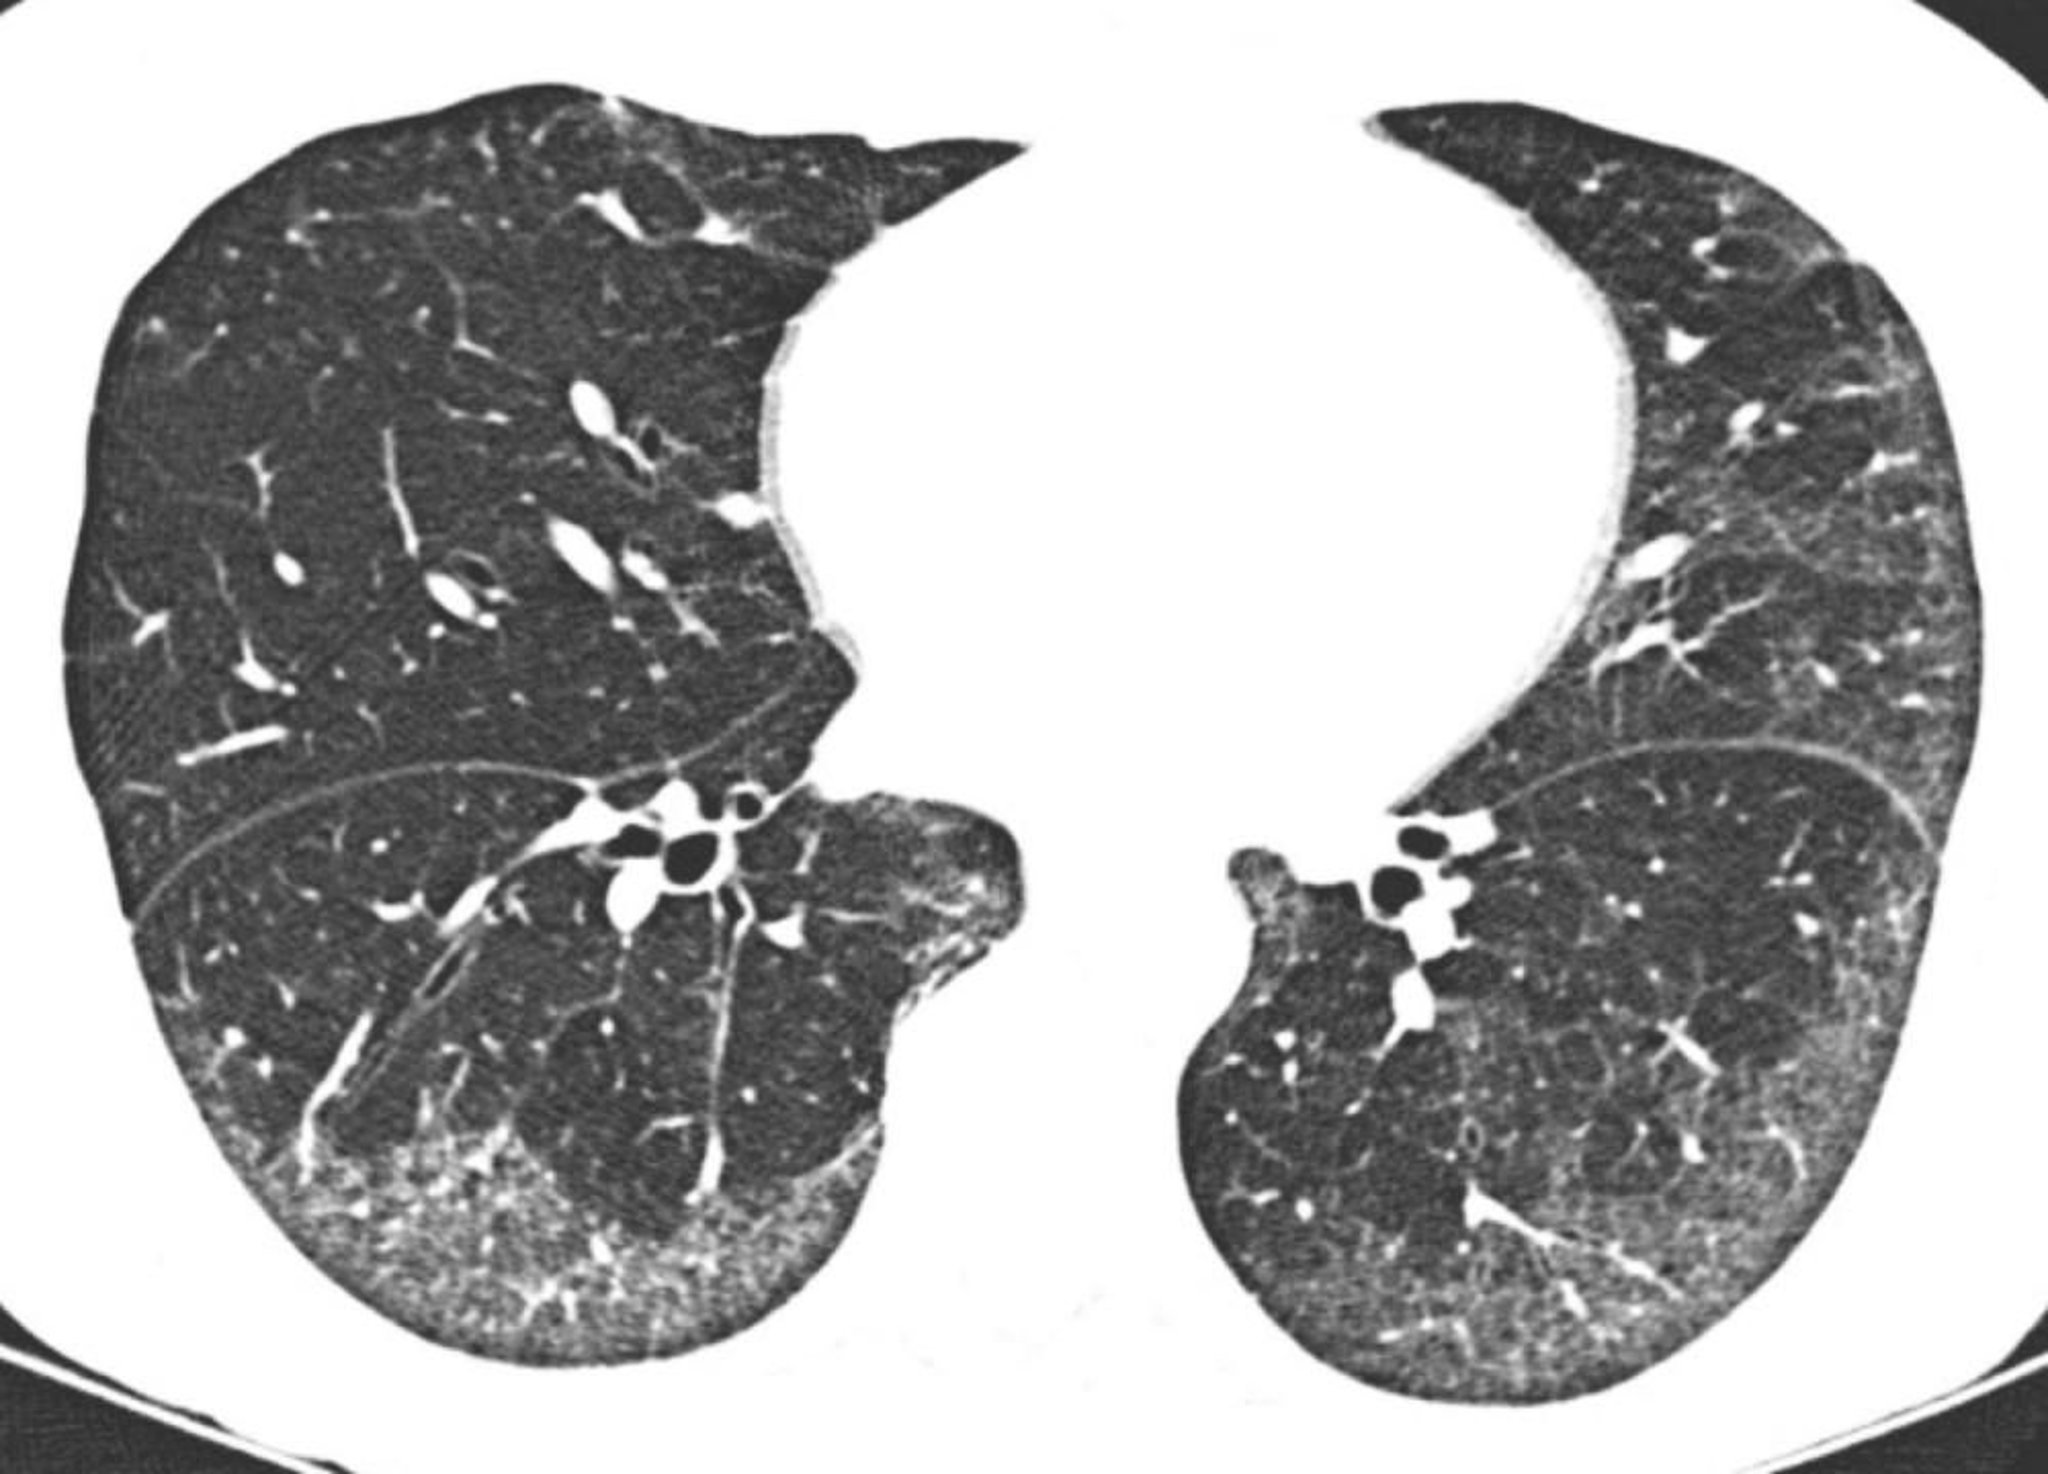

TC de alta resolução mostra opacidades predominantemente subpleurais e basilares em vidro fosco. A relativa preservação do pulmão diretamente abaixo das superfícies pleurais é típica na pneumonia intersticial inespecífica.

Imagem cedida por cortesia de Harold R. Collard, MD.